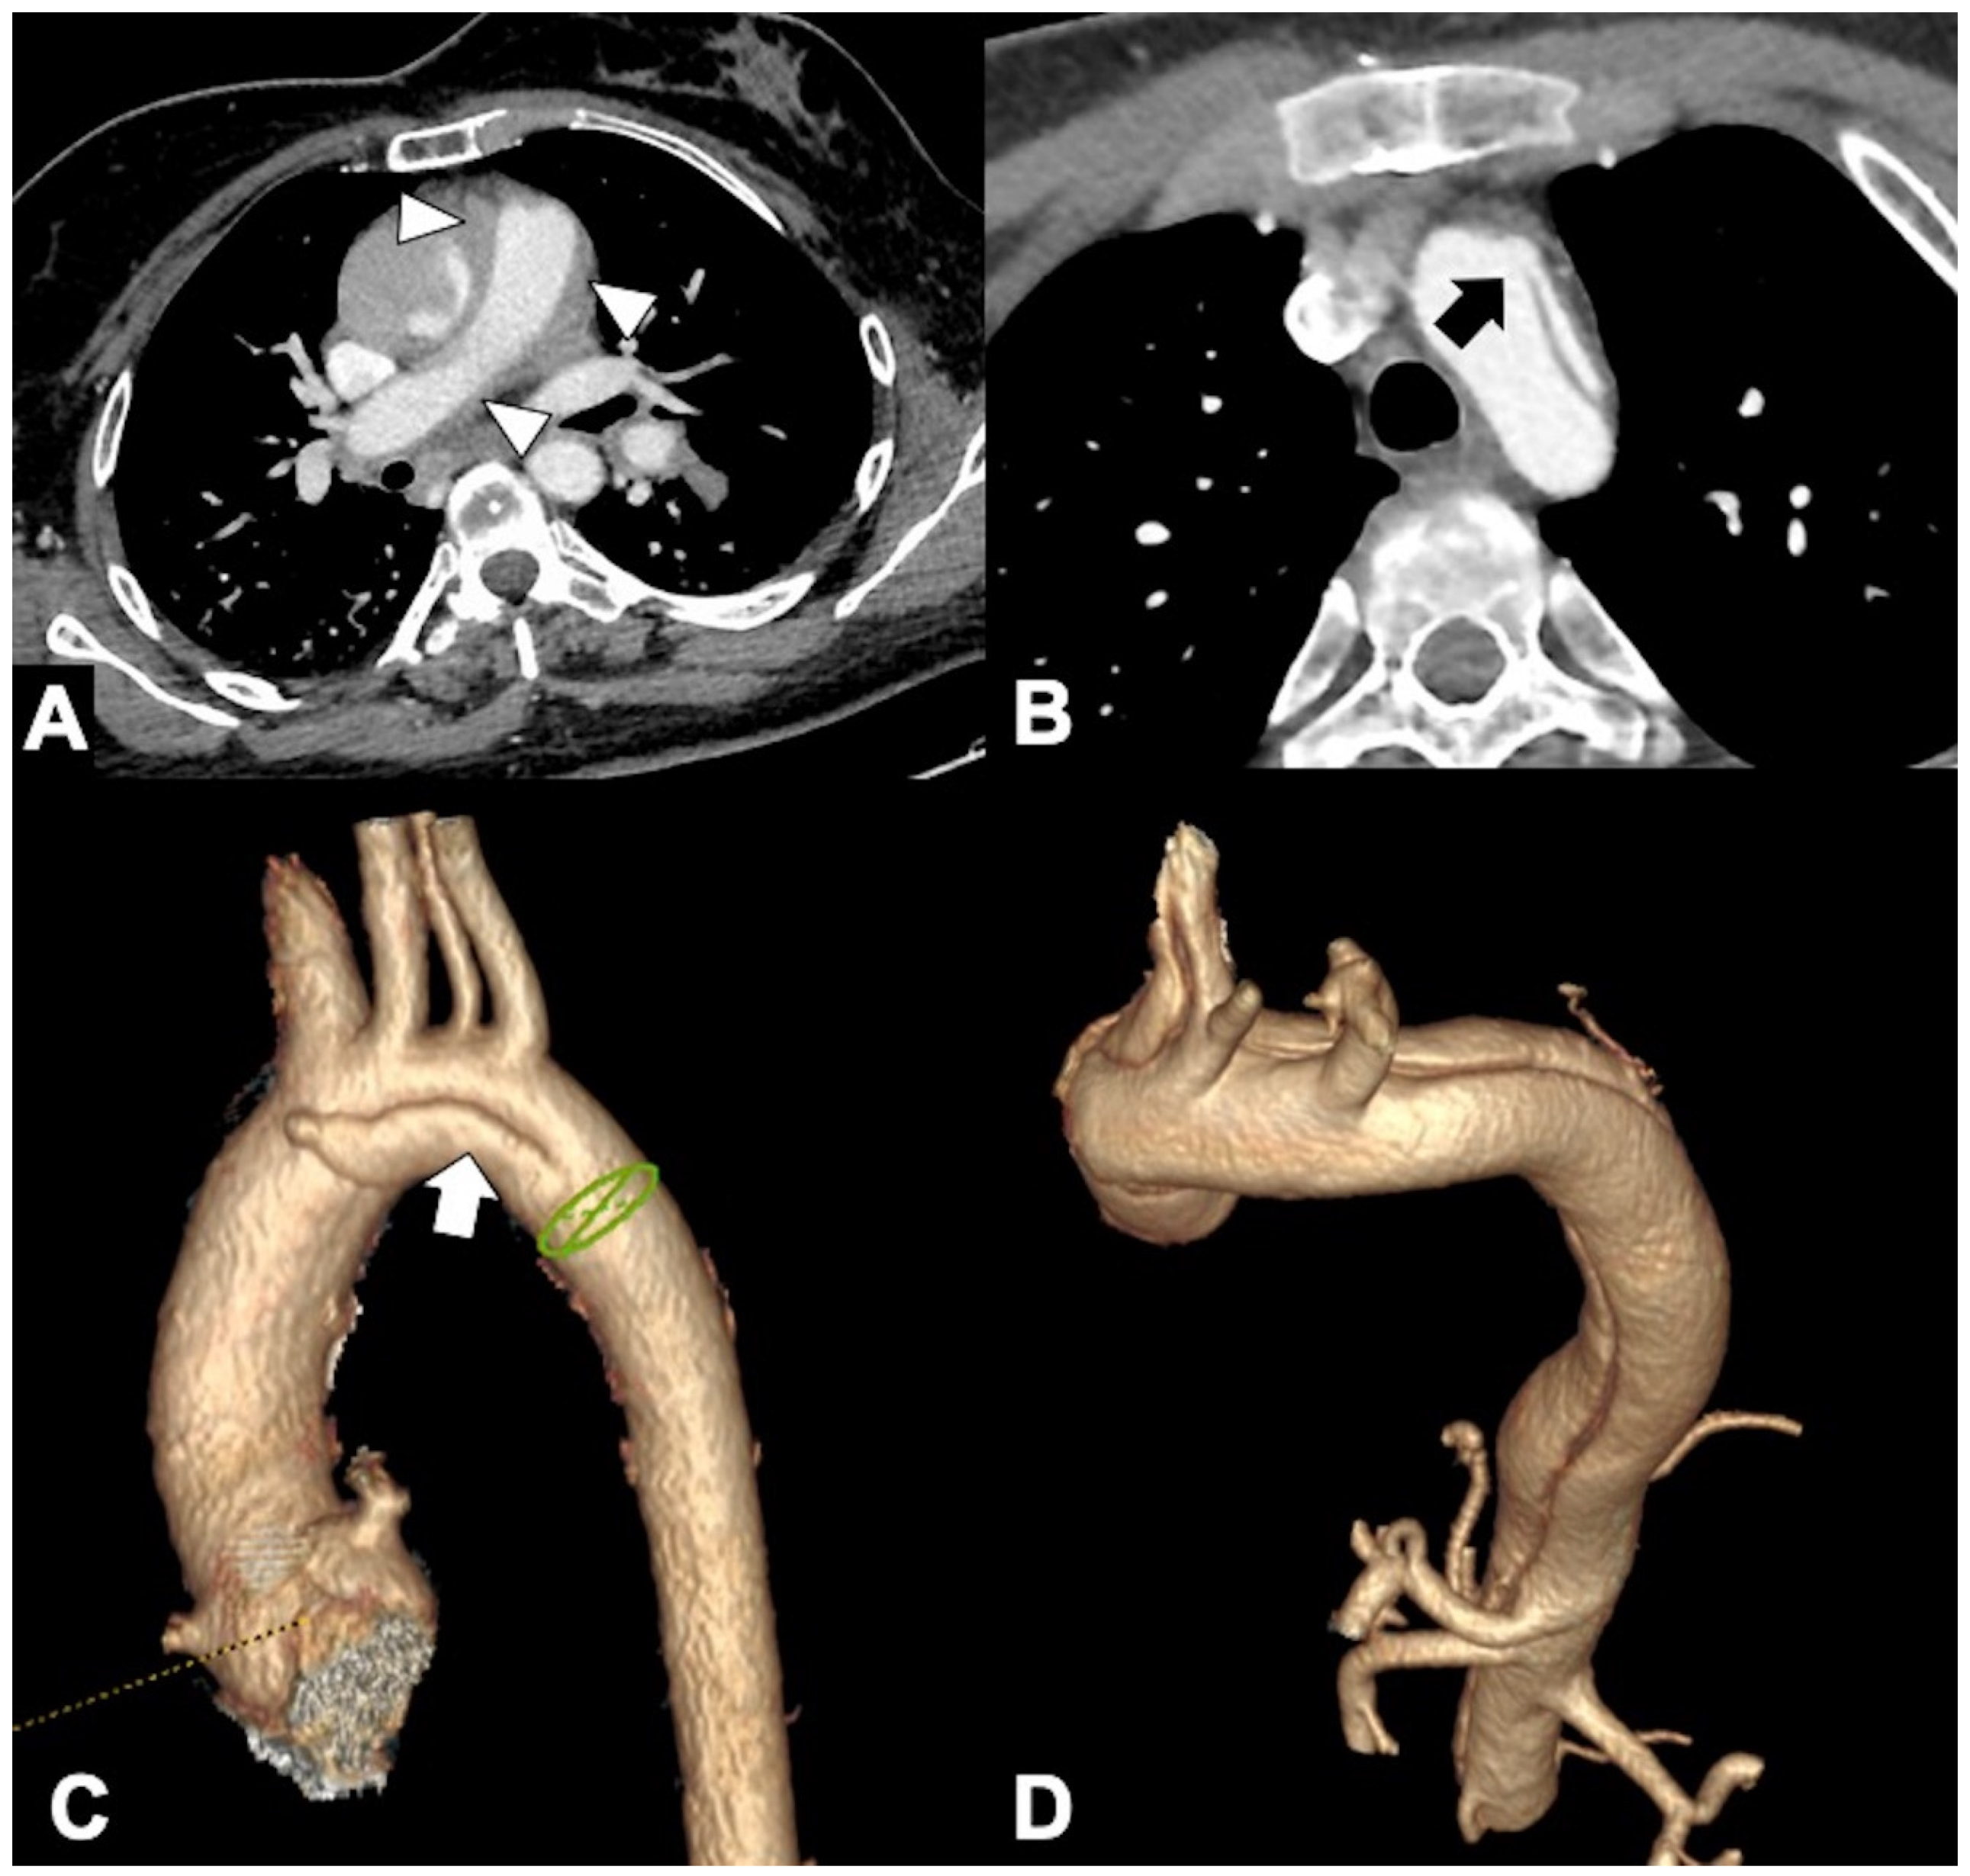

Figure 7. (A) Axial CTA image demonstrates thickening of the main pulmonary arterial wall (arrowheads) indicating IMH of the PA in ruptured Type A AD. (B) Axial CTA image shows entry tear (arrow) in the arch convexity in a 53-year-old man with severe chest pain. (C) 3D-VR parasagittal reconstruction image shows localized 4-vessels arch dissection (arrow) without supra-aortic trunks involvement. (D) 3D-VR parasagittal reconstruction image shows a non-A-non-B dissection with arch-entry and anterograde descending aorta involvement.